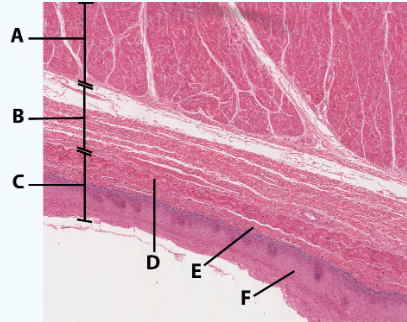

A

Muscularis

B

Submucosa

C

Mucosa

D

Muscularis mucosa

E

lamina propria

F

stratified squamous epithelial tissue

area

Esophagus